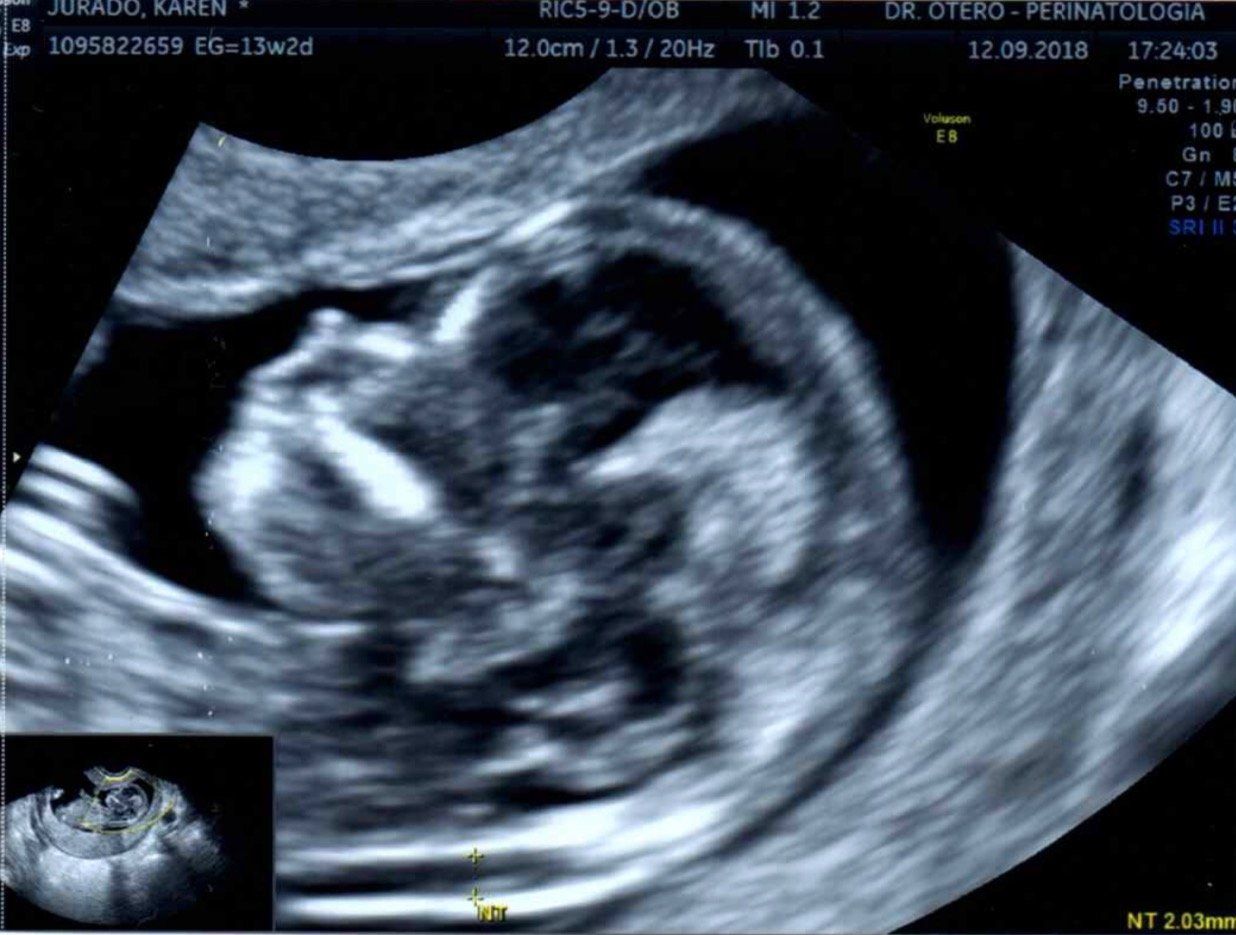

- Ecografías pélvica, transvaginal y obstétrica

- Sonolucencia nucal

El ecógrafo: Voluson® E8 es una plataforma de imágenes que usa tecnología de avanzada, es un sistema de ecografía líder en asistencia sanitaria para mujeres de una nueva generación donde es importante el diagnóstico temprano de malformaciones congénitas para determinar un tratamiento adecuado del feto en pro de su bienestar. La calidad de imagen gracias a sus herramientas vanguardistas nos hace a los perinatólogos los profesionales capaces de intervenir casos difíciles en su manejo. La tecnología HDlives del ecógrafo Voluson e8 expert permite ver el feto en el modo más cercano a una imagen directa sin necesidad de penetrar a la cavidad uterina como se hace en cirugía observando al feto en toda su superficie. El HDlive Ilumina los detalles finos del feto.